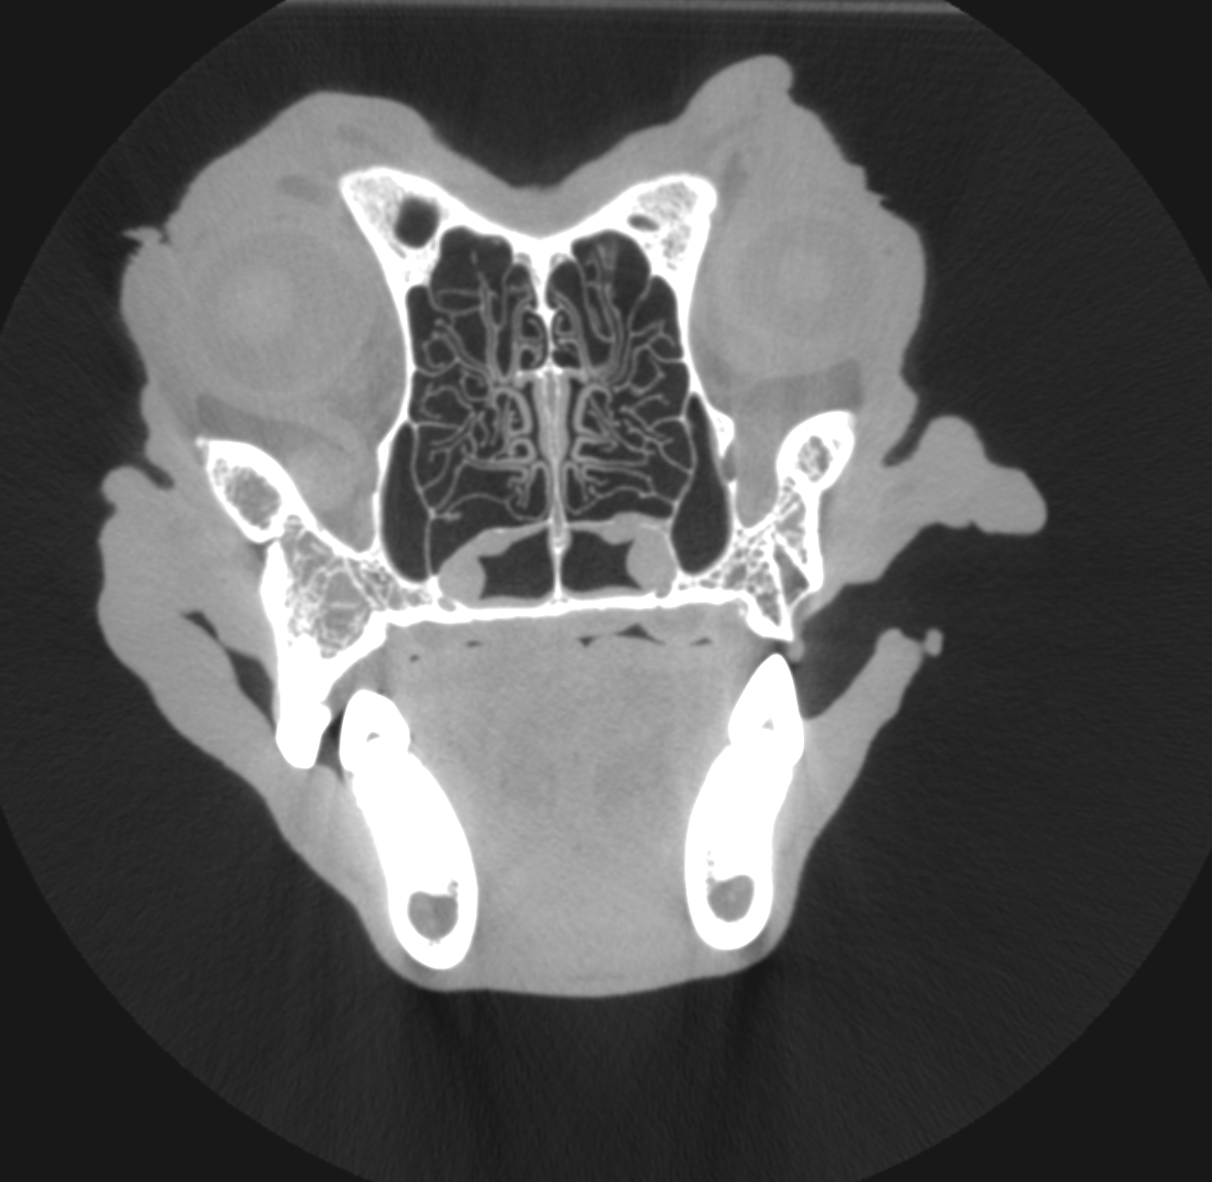

CT (Computed Tomography)

There are many indications for CT scan in animals - such as further evaluation of the nasal cavity, checking for ectopic ureters, finding abnormal vessels, etc.

Cat with a nasal mass - biopsy confirmed lymphoma

Another cat with nasal lymphoma